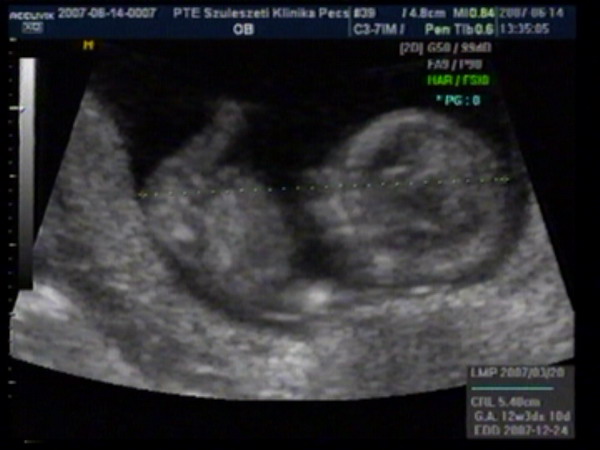

UH-s képeink..

Kép Kép

Júúúúúúúj, de cuki!!!!! És gratula a betöltött 12 héthez!